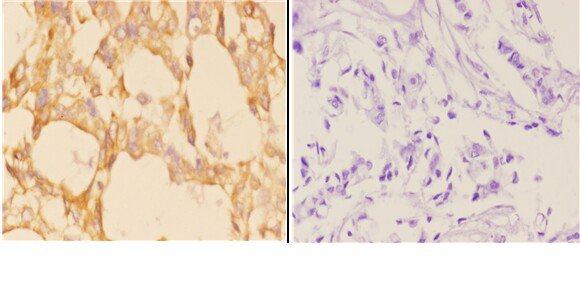

| Gene Name: | ABCB10 |